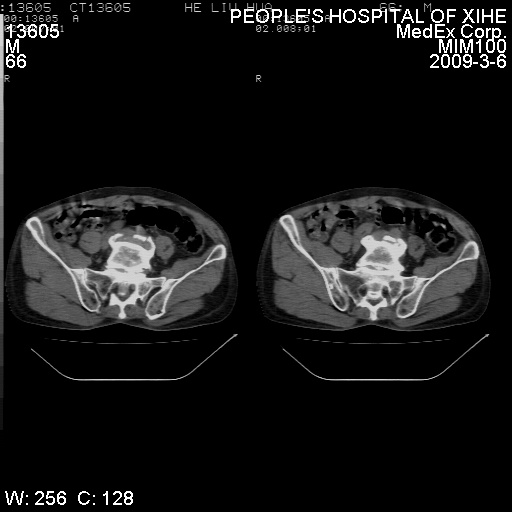

标题: CT18522:男,66岁。考虑结核有错吗 [打印本页]

标题: CT18522:男,66岁。考虑结核有错吗

x线片示:骶骨密度增高。

考虑----腰椎骶化-----退变-----椎管狭窄

腰骶椎退行性改变。

腰骶椎退行性改变,建议重建看看!

退行性变,椎体滑脱

腰椎滑脱并有退变

退行性变,椎体滑脱。建议同椎体平行进一步扫描。